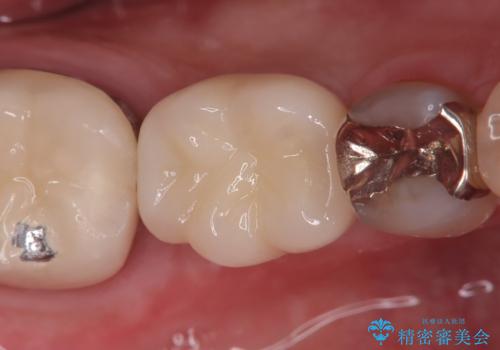

抜歯即時インプラント|切開しないので低侵襲治療|痛く無い治療!

- 当院にて根管治療を行いましたが、病変の改善が得られなかったため、インプラント治療を行う方針といたしました。

抜歯即時埋入の適応と判断し、抜歯当日にインプラント埋入を行う「抜歯即時埋入」にて処置を実施しました。